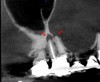

Accurate diagnosis is sometimes the most difficult aspect of daily clinical practice. CBCT has improved the trained practitioner's ability to find hidden periapical pathology, particularly in areas where structures such as the maxillary sinus and zygomatic arch, as well as thick cortical bone, can conceal periradicular lesions (Figure 7 and Figure 8).5-7

Fig 8. 3D CBCT image of tooth No. 3 revealing hidden periapical pathology.

Figure 8